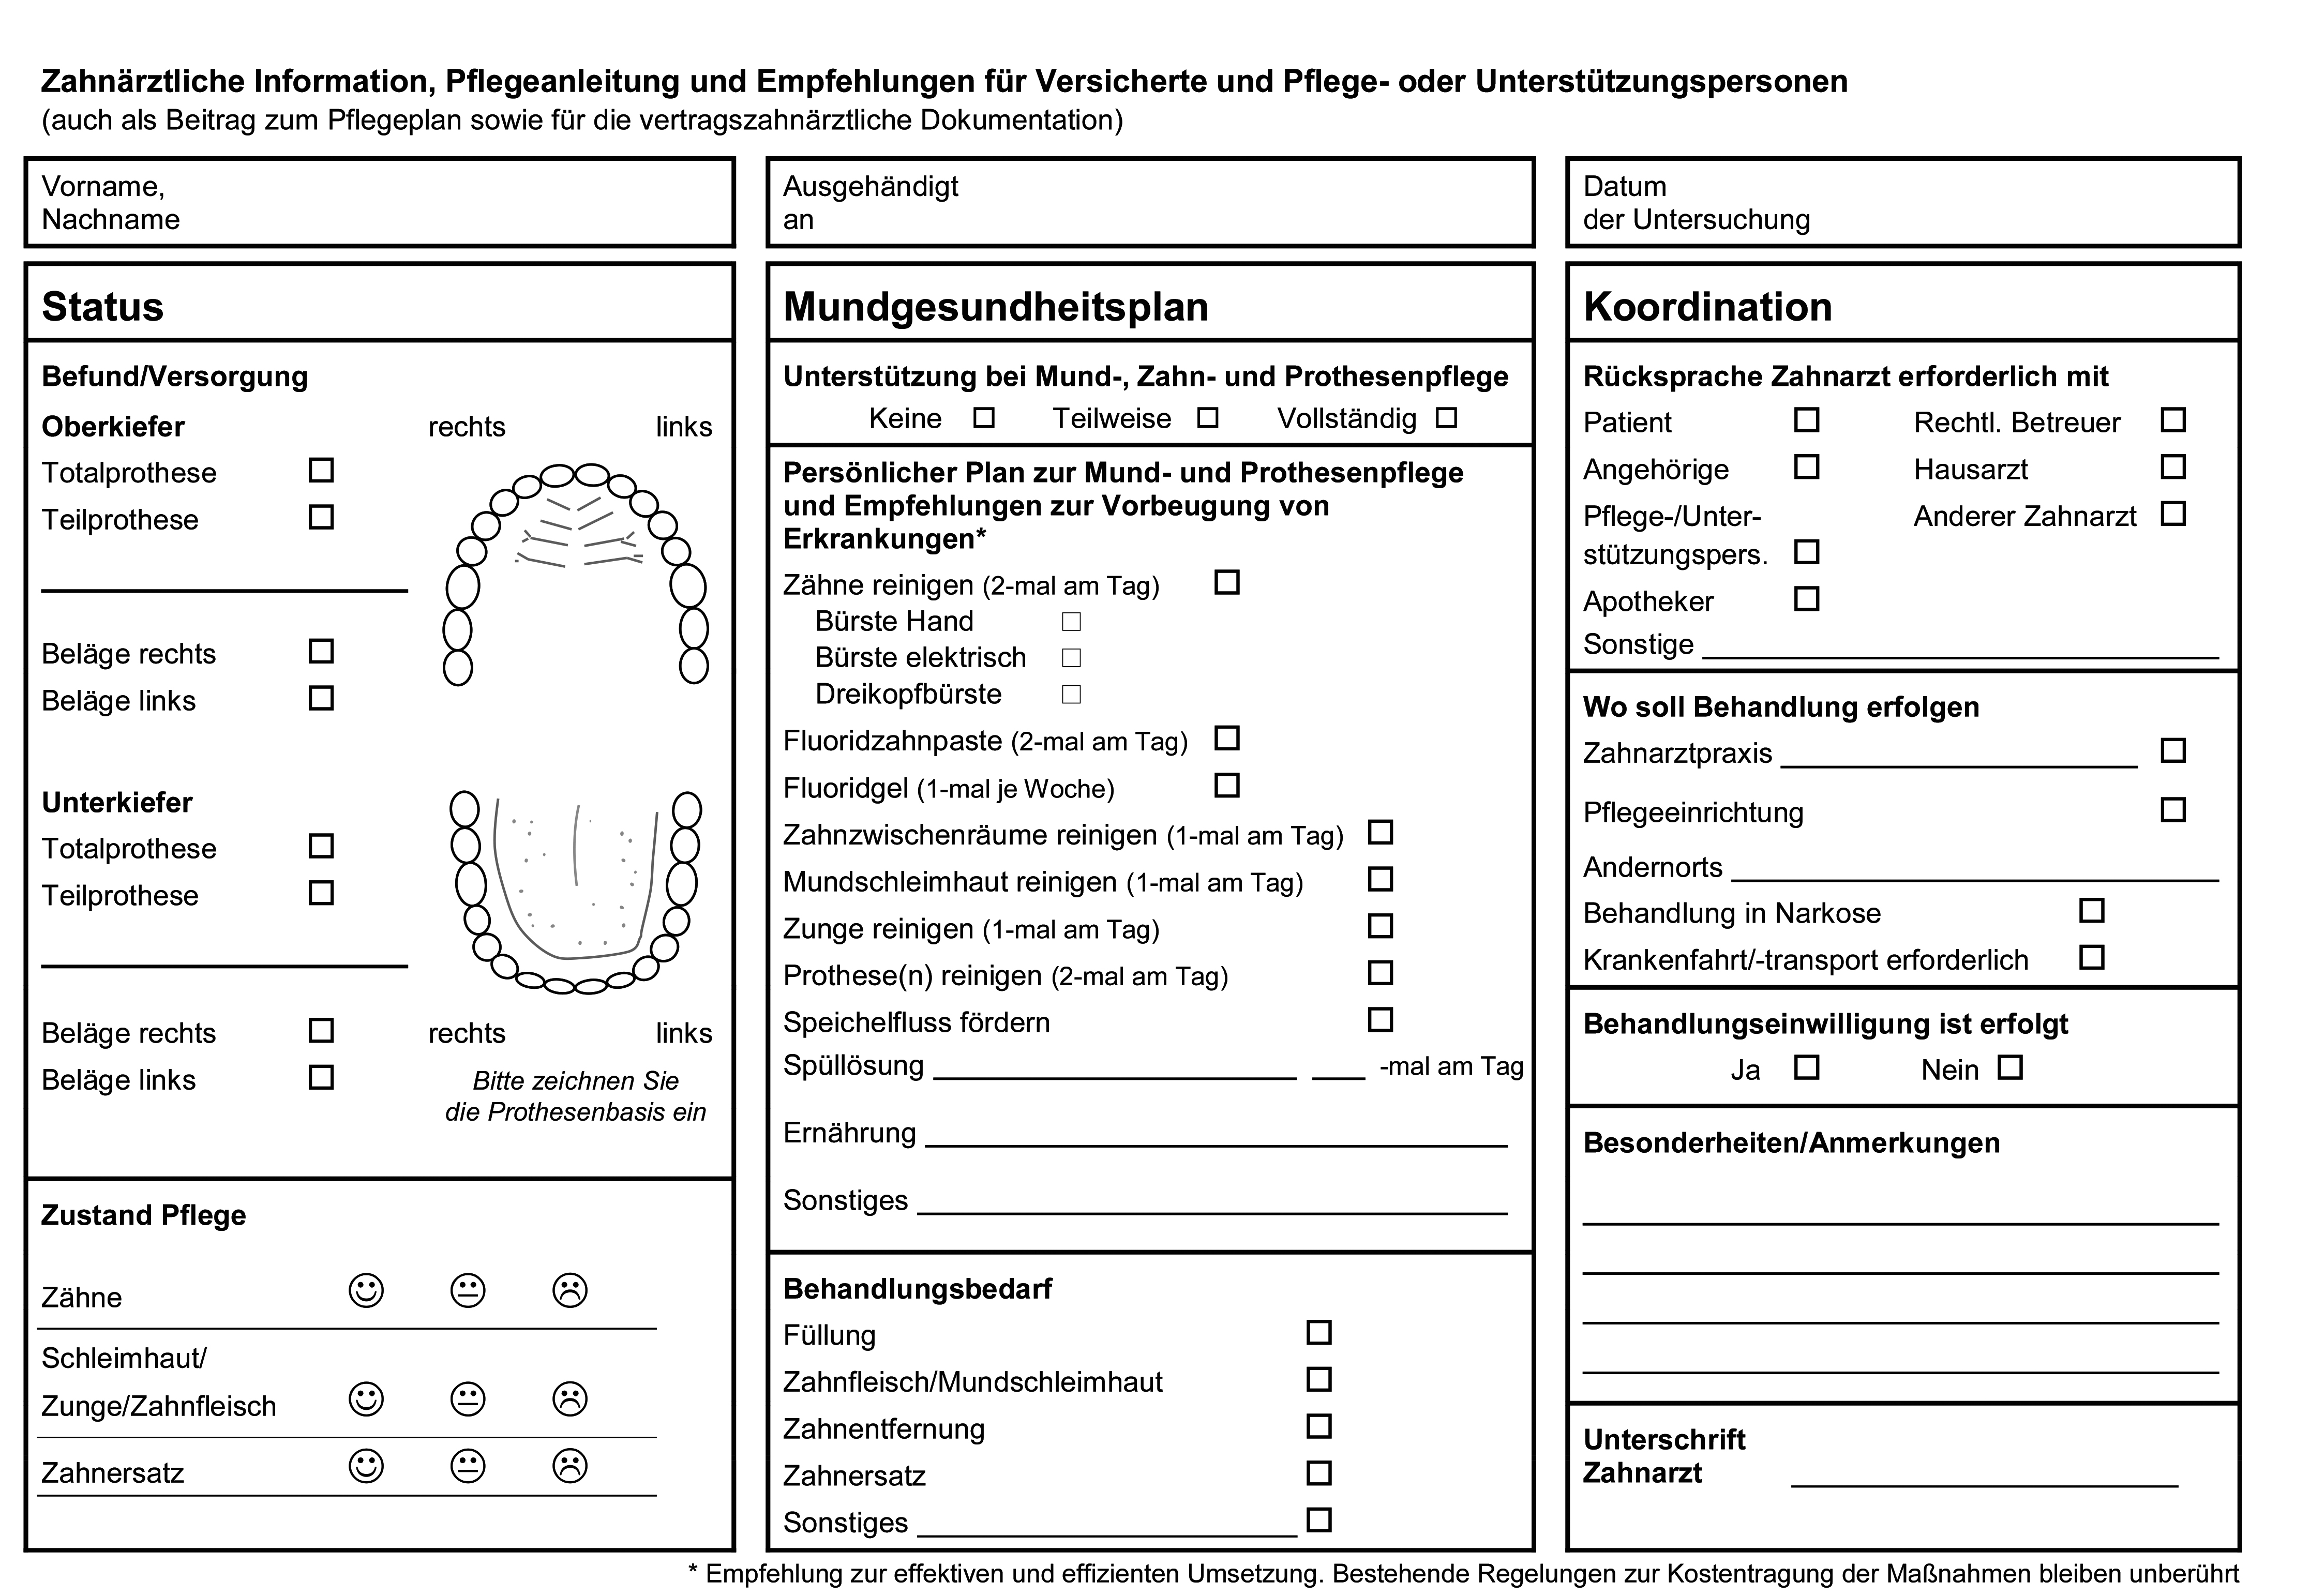

Abrechnung spezieller Präventionsleistungen

Als großer Fortschritt in der Prävention sind die zum Juli 2018 in die BEMA-Gebührenordnung eingeführten präventiven Leistungen für Pflegebedürftige und Menschen mit Behinderung zu sehen. Diese neuen Leistungen (§ 22a Sozialgesetzbuch Abschnitt V – SGB V) können bei Patienten mit zugeordnetem Pflegegrad und für Menschen, die Eingliederungshilfe beziehen, angesetzt werden. Die Leistung kann sowohl in der Zahnarztpraxis als auch bei der aufsuchenden Betreuung zu Hause oder im Pflegeheim einmal pro Kalenderhalbjahr abgerechnet werden. Im Zentrum dieser präventiven Leistungen stehen die Erhebung eines Mundhygienestatus, die Erstellung und Anpassung eines individuellen Mundhygieneplans, die Aufklärung zur Mundgesundheit sowie die Entfernung von Zahnstein.

Sofern der Patient Unterstützung durch eine Pflegekraft oder einen Angehörigen bedarf, sind diese Personen im jeweils erforderlichen Umfang im Rahmen der Mundhygienesitzung einzubeziehen. Im Idealfall ist die Pflegeperson bei den Prophylaxe-Sitzungen anwesend. So können der Pflegeperson unter anderem auch praktische Tipps und Tricks zum Zähneputzen, zur Interdentalraumreinigung und Prothesenreinigung mitgegeben werden. Wird der pflegebedürftige Patient in einer Einrichtung versorgt, können mit Hilfe des Vordrucks gemäß § 8 der Richtlinie des Gemeinsamen Bundesausschusses nach § 22a SGB V zahnärztliche Instruktionen übermittelt werden. Hier lassen sich im Freitext auch Details zur speziellen häuslichen Mundhygiene, z. B. in Bezug auf die Interdentalraumhygiene oder die Prothesenreinigung, thematisieren.